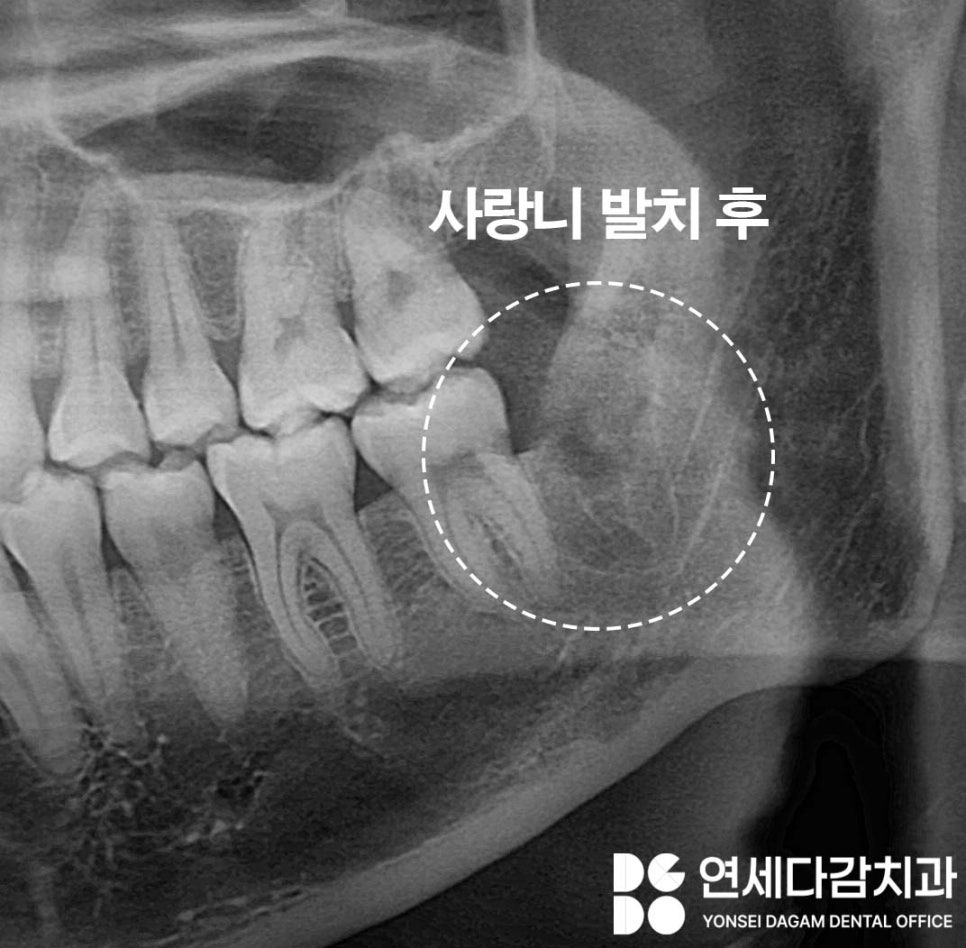

발치가 끝나면

치아가 빠진 자리에 공간이 생깁니다.

이 공간을 발치 와라고 합니다.

대부분은 거즈를 물고 압박하면

자연스럽게 지혈이 됩니다.

그러나 출혈이 많을 것으로 예상되거나

골 삭제 범위가 넓었던 경우에는

지혈제를 발치 와에 넣기도 합니다.

지혈제는 혈액 응고를 도와서

출혈을 조절하는 역할을 합니다.

시간이 지나면 자연스럽게

흡수되거나 빠져나오므로

따로 제거할 필요는 없습니다.